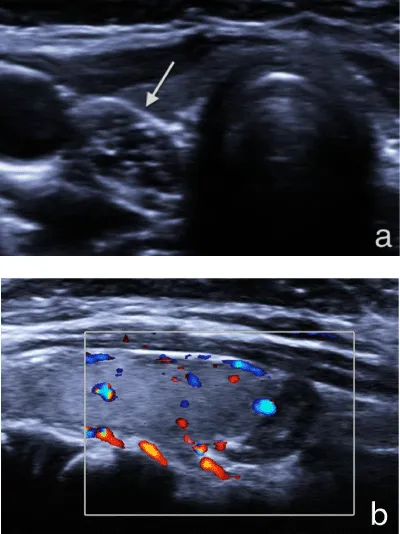

A second ultrasonography was performed in our institution with Siemens Acuson S2000™ ultrasound system using an L9-4 MHz transducer. A 6x6x8 mm sized ovoid lesion in the right lower pole of thyroid was detected. The lesion had no distinct border to thyroid tissue, which leads us to think of an intrathyroidal localization. The lesion was hypoechoic and had multiple milimetric bright internal echoes on gray-scale ultrasonography. Doppler ultrasonography did not show a significant vascularity (Figure 1). Because of the similarity in gray scale and Doppler ultrasonography imaging findings to thymus when compared, the lesion was thought to be an ectopic intrathyroidal thymus (Figure 2). We performed ARFI elastography to support the diagnosis. ARFI elastography measurements from the normal thyroid parenchyma, from the lesion in the right lower pole of thyroid and from the anterior mediastinal thymus were done (Figure 3). Each measurement was repeated for five times and the mean value was recorded. The mean ARFI elastography velocities of the lesion and the mediastinal thymus were, 0, 63 m/s and 0, 60 m/s, respectively. The mean ARFI elastography velocity of the normal thyroid parenchyma was 1, 25 m/s. The normality of data distribution was evaluated with Saphiro-Wilk test and Paired sample T test was used to compare the mean SWVs in normal distributed data. There was not a significant difference between the mean SWV of the lesion and thymus (p=0.9). There was a significant difference between the mean SWV of the lesion and thymus versus thyroid gland (p=0.001 and p=0.002, respectively). The lesion was diagnosed as ectopic intrathyroidal thymus and follow-up was recommended.